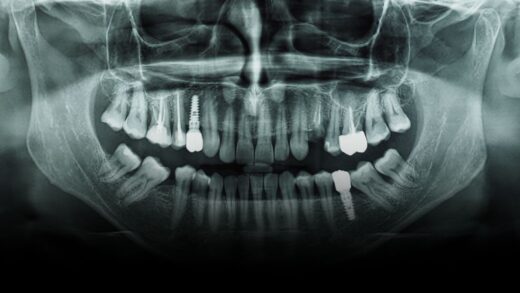

Diseases of the head and neck by Dr Mandana Donoghue

Puzzle 12- Diseases of the head and neck by Dr Mandana Donoghue